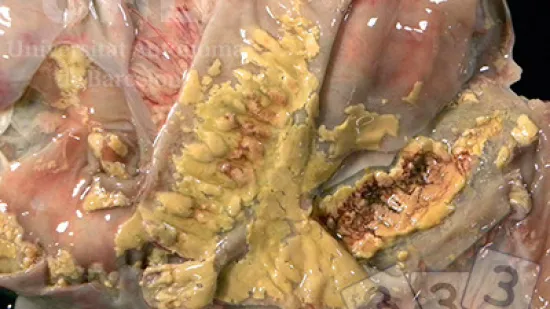

Semaine du 10-Mai-2021

Quelle maladie peut produire cette lèsion ?